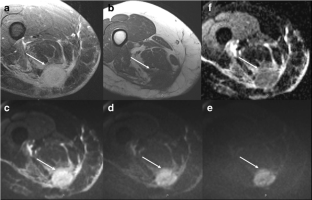

Fig. 3